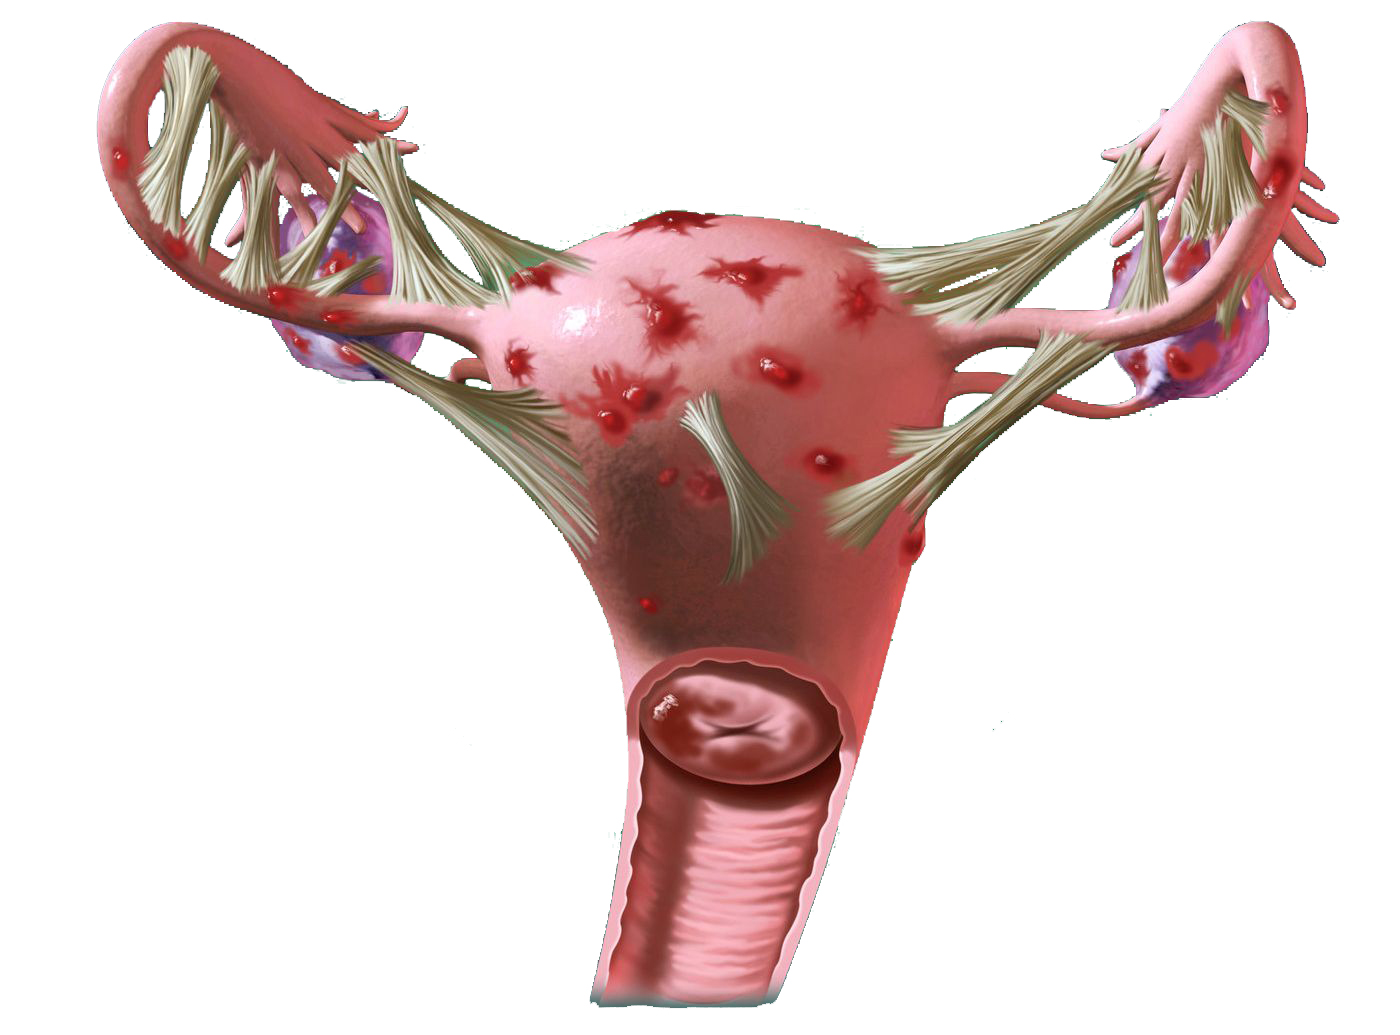

Анатомия женского организма: строение и функции матки